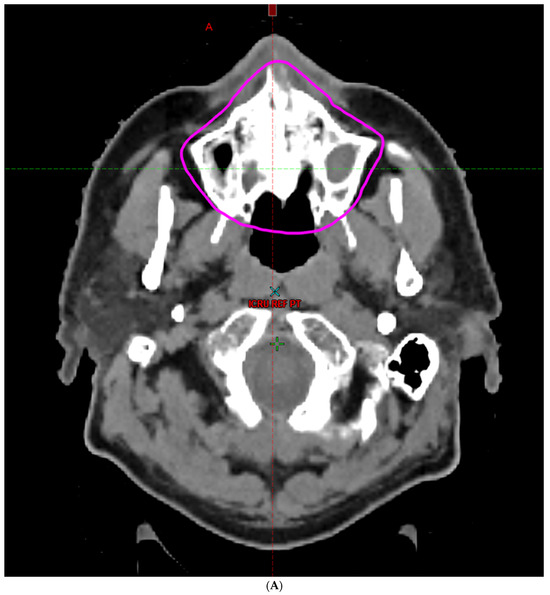

- Hoebers, F.; Yu, E.; Thorstad, W.; O’Sullivan, B.; Dawson, L.A.; Hope, A. A Pragmatic Contouring Guideline for Salivary Gland Structures in Head and Neck Radiation Oncology. The MOIST Target. Am. J. Clin. Oncol. 2013, 36, 70–76. [Google Scholar] [CrossRef]

- Brouwer, C.L.; Steenbakkers, R.J.; Bourhis, J.; Budach, W.; Grau, C.; Grégoire, V.; Van Herk, M.; Lee, A.; Maingon, P.; Nutting, C.; et al. CT-based delineation of organs at risk in the head and neck region: DAHANCA, EORTC, GORTEC, HKNPCSG, NCIC CTG, NCRI, NRG Oncology and TROG consensus guidelines. Radiother. Oncol. 2015, 117, 83–90. [Google Scholar] [CrossRef]

- Li, K.; Yang, L.; Hu, Q.-Y.; Chen, X.-Z.; Chen, M.; Chen, Y. Oral Mucosa Dose Parameters Predicting Grade ≥ 3 Acute Toxicity in Locally Advanced Nasopharyngeal Carcinoma Patients Treated with Concurrent Intensity-Modulated Radiation Therapy and Chemotherapy: An Independent Validation Study Comparing Oral Cavity versus Mucosal Surface Contouring Techniques. Transl. Oncol. 2017, 10, 752–759. [Google Scholar] [CrossRef]

- Sun, Y.; Yu, X.-L.; Luo, W.; Lee, A.W.; Wee, J.T.S.; Lee, N.; Zhou, G.-Q.; Tang, L.-L.; Tao, C.-J.; Guo, R.; et al. Recommendation for a contouring method and atlas of organs at risk in nasopharyngeal carcinoma patients receiving intensity-modulated radiotherapy. Radiother. Oncol. 2014, 110, 390–397. [Google Scholar] [CrossRef]

- Dean, J.A.; Welsh, L.C.; Gulliford, S.L.; Harrington, K.J.; Nutting, C.M. A novel method for delineation of oral mucosa for radiotherapy dose–response studies. Radiother. Oncol. 2015, 115, 63–66. [Google Scholar] [CrossRef]